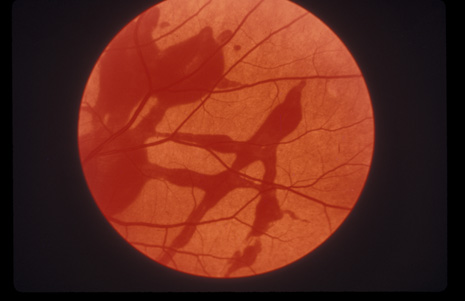

COMMOTIO RETINAE

Commotio retinae (Latin, meaning retinal contusion) is a contrecoup injury. It can occur peripherally (Fig. 8) or centrally, in which case it is called Berlin's edema (Fig. 9). Immediately and for several hours after the trauma, the retina appears normal, although the patient may complain of decreased vision. Thereafter, the outer layers of affected retina become opaque. On fluorescein angiography, the opaque retina blocks background choroidal fluorescence, and in most cases there is no leakage into or under the retina (Fig. 10). For years, clinicians had difficulty explaining this blockage, because leakage is expected in conditions with edema. It was then shown in experimental animals and in human autopsy eyes that Berlin's edema is not true edema. The retinal opaqueness is the result of intracellular edema and fragmentation of the photoreceptor outer segments and intracellular edema of the underlying pigment epithelium. There is little or no intercellular fluid.66–69

Fig. 8. Peripheral commotio retinae. The retinal blood vessels are clearly seen because the retinal whitening is in the outer retinal layers.